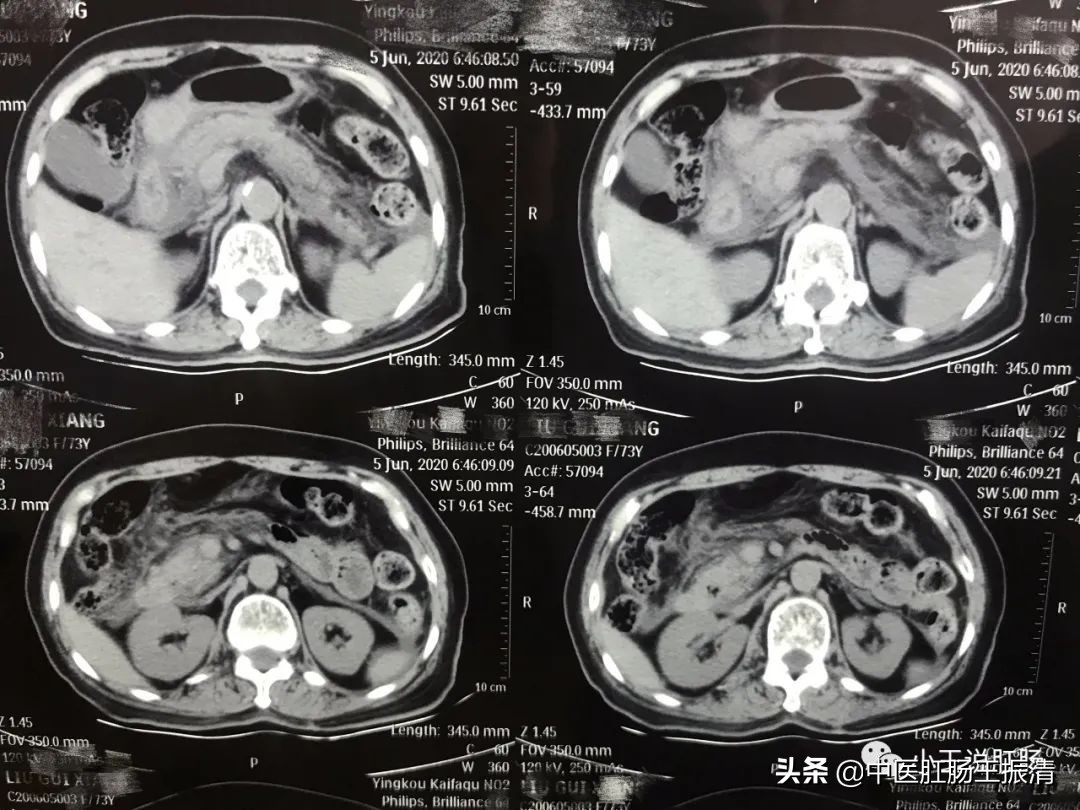

营口市中西医结合医院外一科王振清医生近日收治一位老年患者,刘某,女,73岁,因突发上腹痛8小时,疼痛难忍,急诊入院治疗,入院时体温39°c,伴恶心呕吐,急查上腹CT示(下图)胆囊增大,胆囊结石,急性胰腺炎伴有积液,血清淀粉酶急剧升高,给予禁食水、胃肠减压、抗炎、补液、抑酸等对症治疗,现病情平稳。

该患者既往有胰腺炎病史,胆囊炎,胆石症,还有糖尿病,确诊该患者为急性胆源性胰腺炎,目前刘阿姨可谓是从死神里拉了回来,所以警惕大家,不要小瞧胰腺炎,重者可致命哦!